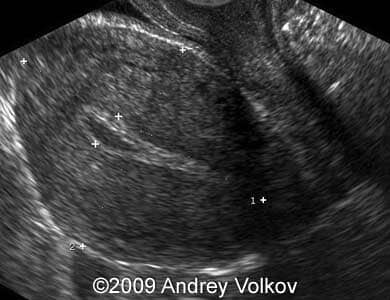

Images 1, 2: The image 1 shows the sac of the extrauterine pregnancy located within the in the myometrium of the right uterine corner. The endometrium of the uterus was thick (17.7 mm) and hyperechoic. The gestational sac measured 34.5 x 31.8 mm). The image 2 shows the embryo within the gestational sac (CRL 8.2 mm, corresponding to 6 weeks and 4 days of pregnancy).